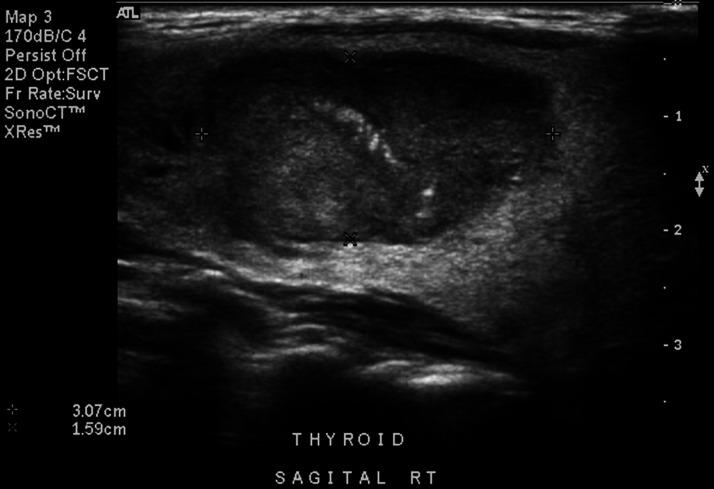

Sonographic Findings of Medullary Thyroid Carcinoma Leading to Diagnosis of Multiple Endocrine Neoplasia Type 2a during Pregnancy.

Multiple endocrine neoplasia (MEN) type 2a (Sipple's syndrome) is characterized by medullary thyroid carcinoma and pheochromocytoma, and in a smaller percentage of cases, multiglandular parathyroid hyperplasia. This autosomal-dominant syndrome is due to a mutation in the rearranged during transfection (RET) proto-oncogene located on chromosome 10cen-10q11.2 and rarely complicates pregnancy. We present an unusual case in a patient with an enlarged thyroid with sonographic findings characteristic of thyroid cancer, which led to diagnosis and subsequent management of RET proto-oncogene-positive MEN type 2a complicating pregnancy.